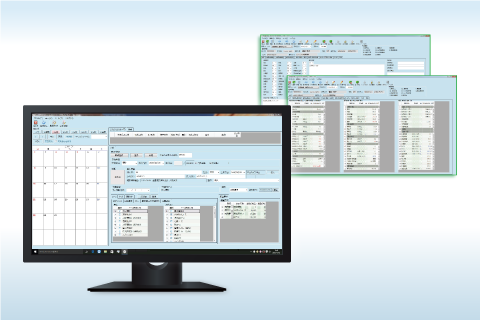

線量管理 健診システム

健診システム 放射線レポート

検査システム 健診システム

健診システム FORZ-HWS(クラウドサービスシステム)